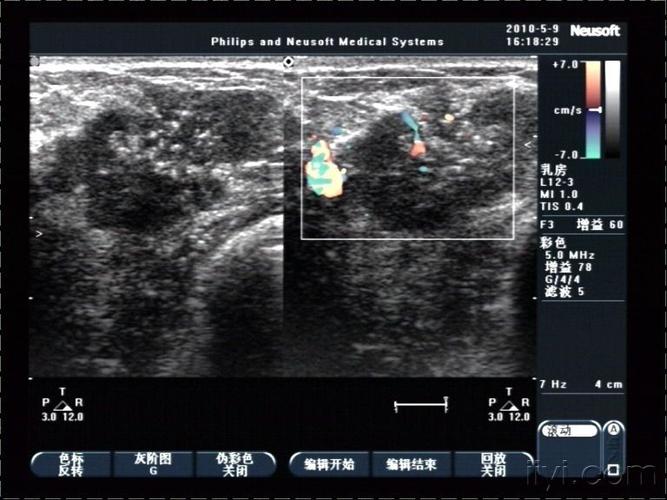

超声乳腺疾病欣赏

汇总史上最详细乳腺恶性肿瘤的超声诊断有图有真相

乳腺癌典型声像图 - 超声医学讨论版 - 爱爱医医学论坛

浸润性乳腺癌图片

浸润性乳腺癌